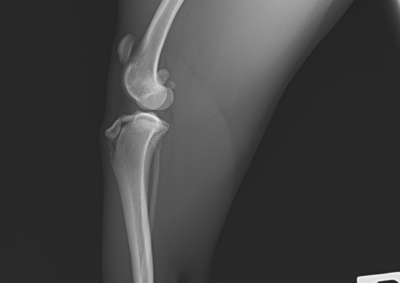

整形外科 注意 ボタンをクリックした先に、治療中および手術中の画像が説明で使用されている場合がございます。 そのような画像に弱い方は閲覧なさらないようお願いいたします。 整形外科 橈骨固定術 #251 整形外科 膝蓋骨高位に対する脛骨粗面遠位化術 整形外科 ミニチュアダックスの脛骨遠位内反矯正+膝蓋骨外方脱臼 整形外科 橈骨固定術 #250 整形外科 股関節脱臼に対するトグルロッド整復術 #64 整形外科 橈骨固定術 #249 整形外科 橈骨固定術 #248 整形外科 内側鉤状突起分離症 FCP 整形外科 橈骨固定術 #247 整形外科 膝蓋骨内方脱臼G3に対する人工滑車(PGR)#20 整形外科 CBLO #239 整形外科 股関節脱臼に対する大腿骨頭頸部切除術 <12345678910> 症例カテゴリー 放射線治療整形外科軟部組織外科脳神経外科内科腫瘍外科救急・集中治療リハビリテーション科腫瘍内科内視鏡科脳神経科呼吸器外科中医・漢方猫の腎移植循環器科